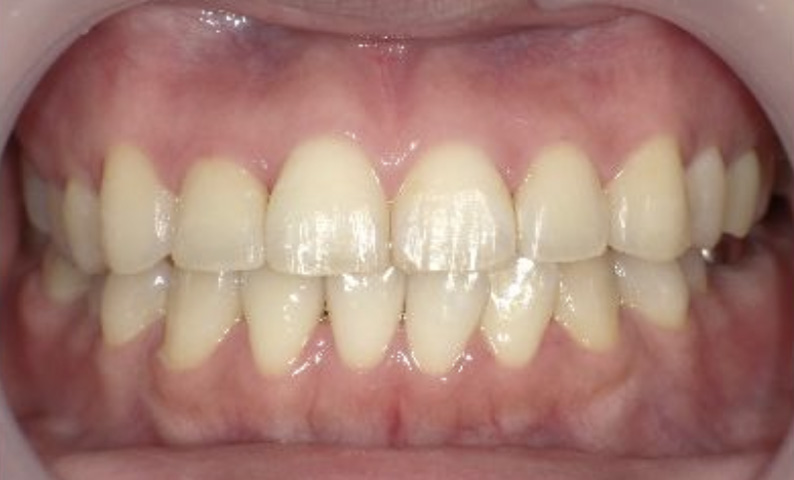

症例_025 上下顎の部分矯正

治療期間:13ヶ月金額:51万円+税女性前歯のガタガタ出っ歯

| Before | After |

|---|---|

|